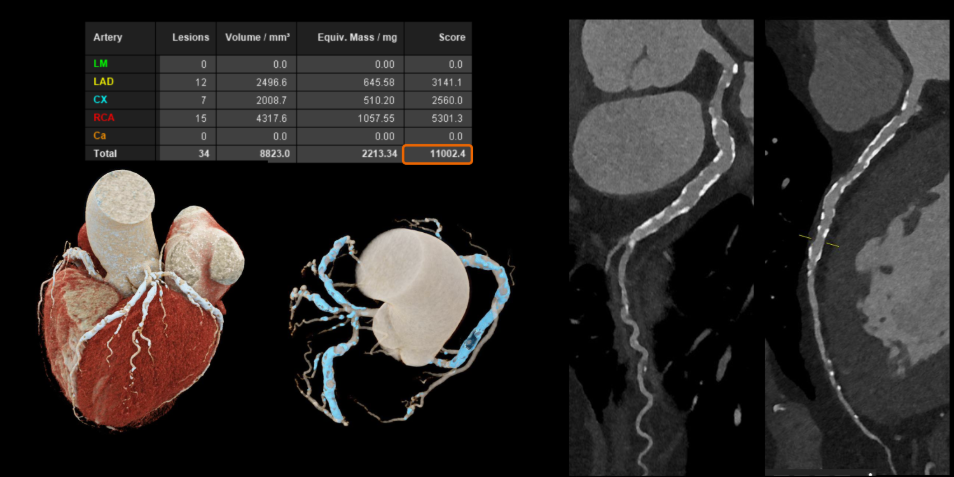

Với các bệnh tim mạch, đặc biệt ở những bệnh nhân đã đặt stent hoặc có mạch vành bị vôi hóa nặng – vốn là những trường hợp khó đánh giá bằng CT thông thường. Công nghệ này cho phép hình ảnh rõ ràng hơn đáng kể. Nhờ đó, bác sĩ có thể quan sát chính xác lòng mạch và các mảng xơ vữa, ngay cả khi bệnh nhân có nhịp tim cao hoặc loạn nhịp mà không cần sử dụng thêm thuốc hỗ trợ.

Hình ảnh mạch vành cho thấy độ rõ cao hơn, giảm nhiễu và giúp đánh giá chính xác hơn (Nguồn: Siemens Healthineers)